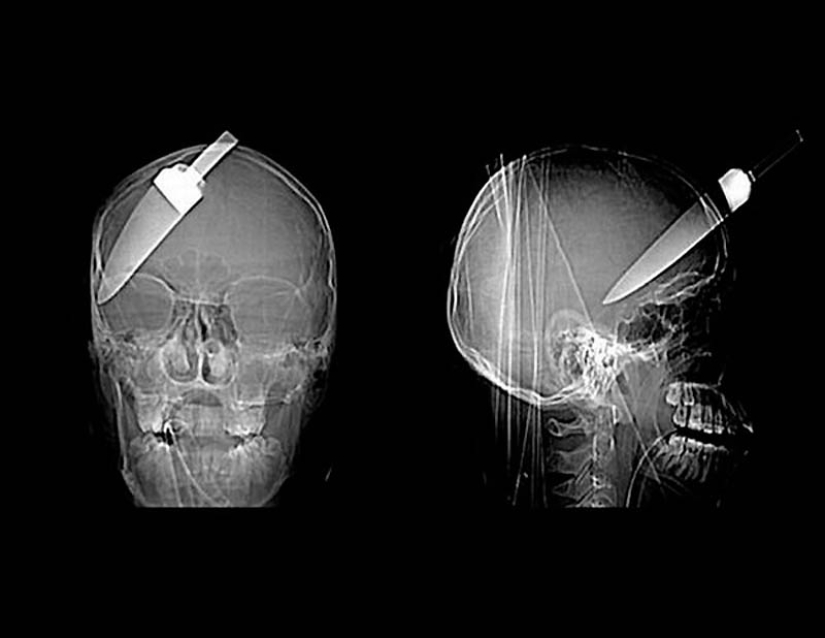

15. Un cuchillo en la cabeza de un niño de 10 años. El chico sobrevivió.

18. un cuchillo de 12 centímetros en el cráneo de un adolescente.